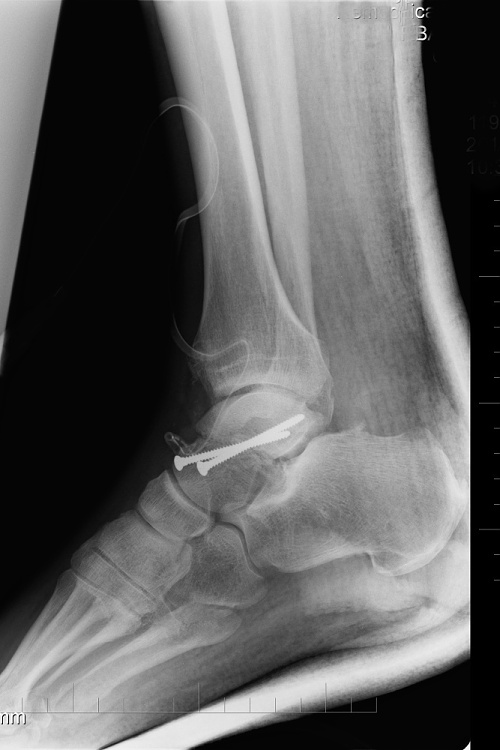

Pak už následují ty obligátní věci jako injekce, rentgeny, operace ... bilance je neslavná. Zlomené hlezno a rozdrcená pata na pravé noze, otevřená zlomenina kotníku s vyhozeným kloubem, zlomené hlezno na levé. To bude asi na dlouho.

Moje nožičky

foto by © Archive Aldo